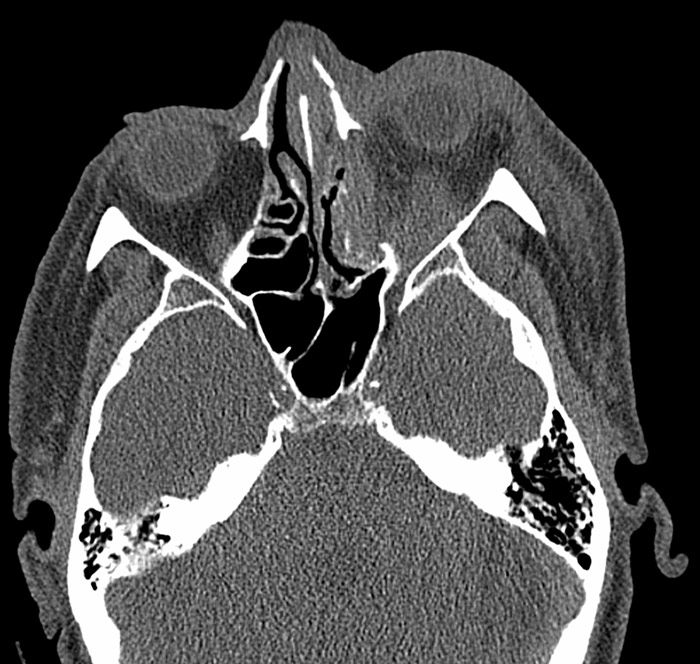

En mann i 60-årene ble innlagt etter en fallskade med traume mot ansiktsregionen. CT av ansikt viste nesefraktur, venstresidig fraktur av orbitagulvet og mediale orbitavegg med dislokasjon samt intraorbitalt hematom. Bulbus var intakt (bildet til venstre). Klinisk undersøkelse viste venstresidig periorbitalt hematom og uttalt proptose. Ved palpasjon var venstre øye spent uten elastisitet. Det forelå svært innskrenket øyebevegelighet av venstre øye i samtlige blikkretninger, nærmest oftalmoplegi. Det var verken direkte eller indirekte lysreaksjon og fullstendig tap av synet på venstre øye. Intraokulært trykk på venstre øye var målt til 70 mm Hg.

Vår pasient oppfylte alle kriterier for traumatisk retrobulbær blødning. Fire timer etter innkomst ble det utført dekompresjon ved lateral kantotomi og kantolyse i lokalanestesi (åpning av laterale øyevinkel og spalting av det laterale kantale ligament) (bildet til høyre). Etter operasjonen gikk proptosen raskt tilbake og etter 15 minutter var det intraokulært trykk på 20 mm Hg. Pasienten fikk dessverre ikke bedre syn i dette tilfellet. Traumatisk optikusnevropati vurderes derfor som en mulig tilleggsdiagnose.